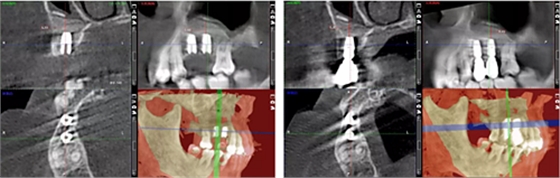

術后14個月